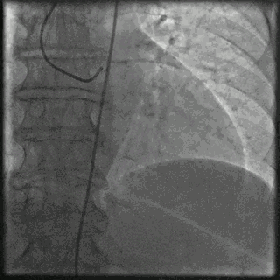

(2) Étapes spécifiques : le patient est allongé sur le lit d'opération dans le laboratoire de cathétérisme cardiaque, le site de l'opération est désinfecté (main ou cuisse), un anesthésique local est administré dans cette zone, un trou est pratiqué dans le vaisseau sanguin artériel à l'aide d'une aiguille, un fil-guide fin et un cathéter sont envoyés, et le cathéter à fil-guide peut atteindre les artères coronaires en suivant les vaisseaux sanguins sous le contrôle de la radiographie, puis un type de médicament (agent de contraste) est injecté dans la tête du cathéter fin, ce qui fera apparaître les vaisseaux sanguins sous les rayons X, et la taille, le trajet, l'obstruction n'est pas visible, les artères coronaires gauche et droite, chaque branche, etc. d'un seul coup d'œil. Les vaisseaux sanguins apparaissent sous la radiographie et l'on peut voir d'un seul coup d'œil leur taille, leur trajet, s'ils sont obstrués ou non, ainsi que les artères coronaires gauche et droite et les différentes branches des artères. Si le problème n'est pas grave, c'est la fin, on retire le cathéter, on ponctionne le poignet à l'aide d'un compresseur pour éviter les saignements. L'ensemble du processus prend 10 à 30 minutes si vous êtes compétent. Si le problème est grave, le traitement (dilatation par ballonnet, pose d'un stent, etc.) peut se poursuivre et prendre plus de temps.

Car l'imagerie consiste bien sûr à injecter une certaine quantité de produit de contraste dans les vaisseaux coronaires de notre cœur, et nous pouvons ensuite observer les cavités de notre cœur ainsi que les vaisseaux sanguins, etc. sous l'irradiation de nos rayons X.C'est alors qu'il faut trouver une ouverture dans les artères coronaires du cœur pour y pomper du produit de contraste, et cette ouverture est une opération invasive !

présent .Plus de 95 % des patients partent de l'artère radiale du poignet.Le médecin insère un tuyau de l'artère radiale dans l'ouverture de l'artère coronaire et l'envoie dans l'ouverture de l'artère coronaire de notre cœur, puis il ouvre le produit de contraste et l'irradie avec des rayons X, de sorte que les vaisseaux sanguins du cœur peuvent être clairement vus, et notre médecin, en observant le développement de l'image, peut juger si les artères du cœur sont rétrécies, si elles sont obstruées ou non, et, si elles sont obstruées, à quel point le sont-elles ? À partir de là, nous pouvons déterminer si nous souffrons d'une maladie coronarienne ou d'autres maladies cardiaques !

Il s'agit d'une ponction de l'artère radiale de la main ou de l'artère fémorale à la racine de la cuisse, le cathéter sera envoyé le long des vaisseaux sanguins artériels, a été étendu aux artères coronaires, injecté dans l'agent de contraste, l'agent de contraste sera mélangé à nos artères coronaires du sang, rempli avec les artères coronaires, les vaisseaux sanguins dans la radiographie n'est pas visible, mais après l'injection de l'agent de contraste, peut être visible sous la radiographie, nous serons en mesure d'observer la situation des vaisseaux sanguins pour voir la situation des blocages, de la sténose, de la plaque ! Nous pouvons alors examiner le vaisseau sanguin pour voir s'il y a un blocage, un rétrécissement ou une plaque !